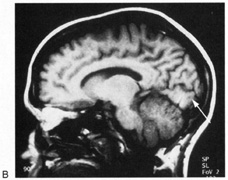

Fig. 9. Macular-sparing striate hemianopia. A 49-year-old woman with headache and difficulty seeing to the left for 1 week. A. Fields show left hemianopia that spares a small zone around the central fixation spot. B. Magnetic resonance imaging shows infarct of right striate cortex, with sparing of occipital pole. (From Rosen ES, Eustace P, Thompson HS, Cumming WJK [eds]: Neuro-Ophthalmology. London: Mosby, 1998.)

The upper and lower banks can also be involved separately. Ischemia can do this because the banks have separate blood supplies. Upper bank infarcts cause homonymous contralateral inferior quadrantanopia (Fig. 10) and lower bank infarcts cause superior quadrantanopia. Although altitudinal defects have been reported occasionally,47,48 most quadrantic defects do not align at the horizontal meridian, because the upper field merges without interruption into the lower field in the depths of the calcarine fissure. Thus it has been argued that quadrantic defects that respect the horizontal meridian are caused by involvement of area V2, surrounding striate cortex,49 which remains controversial. Quadrantanopias are three times more common with striate lesions than with optic radiation lesions.33 Striate quadrantanopias are more frequently isolated signs but can be associated with other signs of higher cortical visual dysfunction, such as pure alexia or hemiachromatopsia, whereas optic radiation quadrantanopias usually are accompanied by hemiparesis, dysphasia, or amnestic problems.33